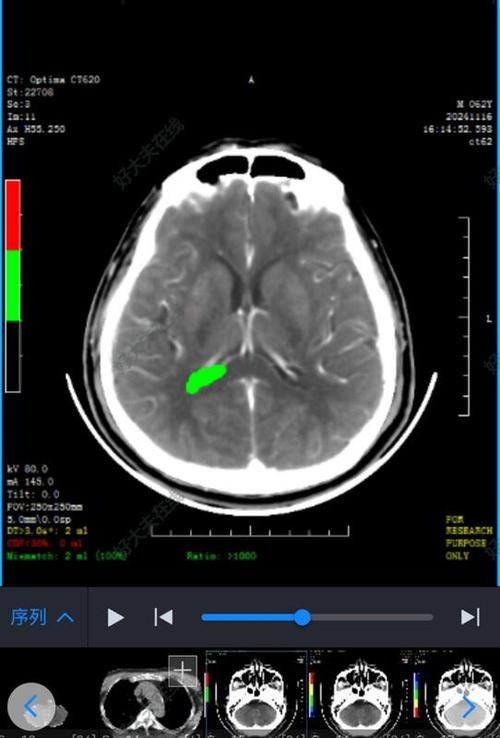

亚急性期(发病3天 - 2周)—— CT表现最典型

这是CT诊断脑梗的“黄金时期”,脑组织水肿达到顶峰,坏死区域变得非常清晰。

- CT表现:

- 明显的低密度灶: 梗死区域在CT上呈现为边界清晰、形态与相应供血动脉分布一致的低密度影,这是脑梗在CT上最典型的表现。

- 占位效应: 严重的水肿会导致脑组织受压,中线结构(如大脑镰)移位,这是判断病情严重程度的重要指标。